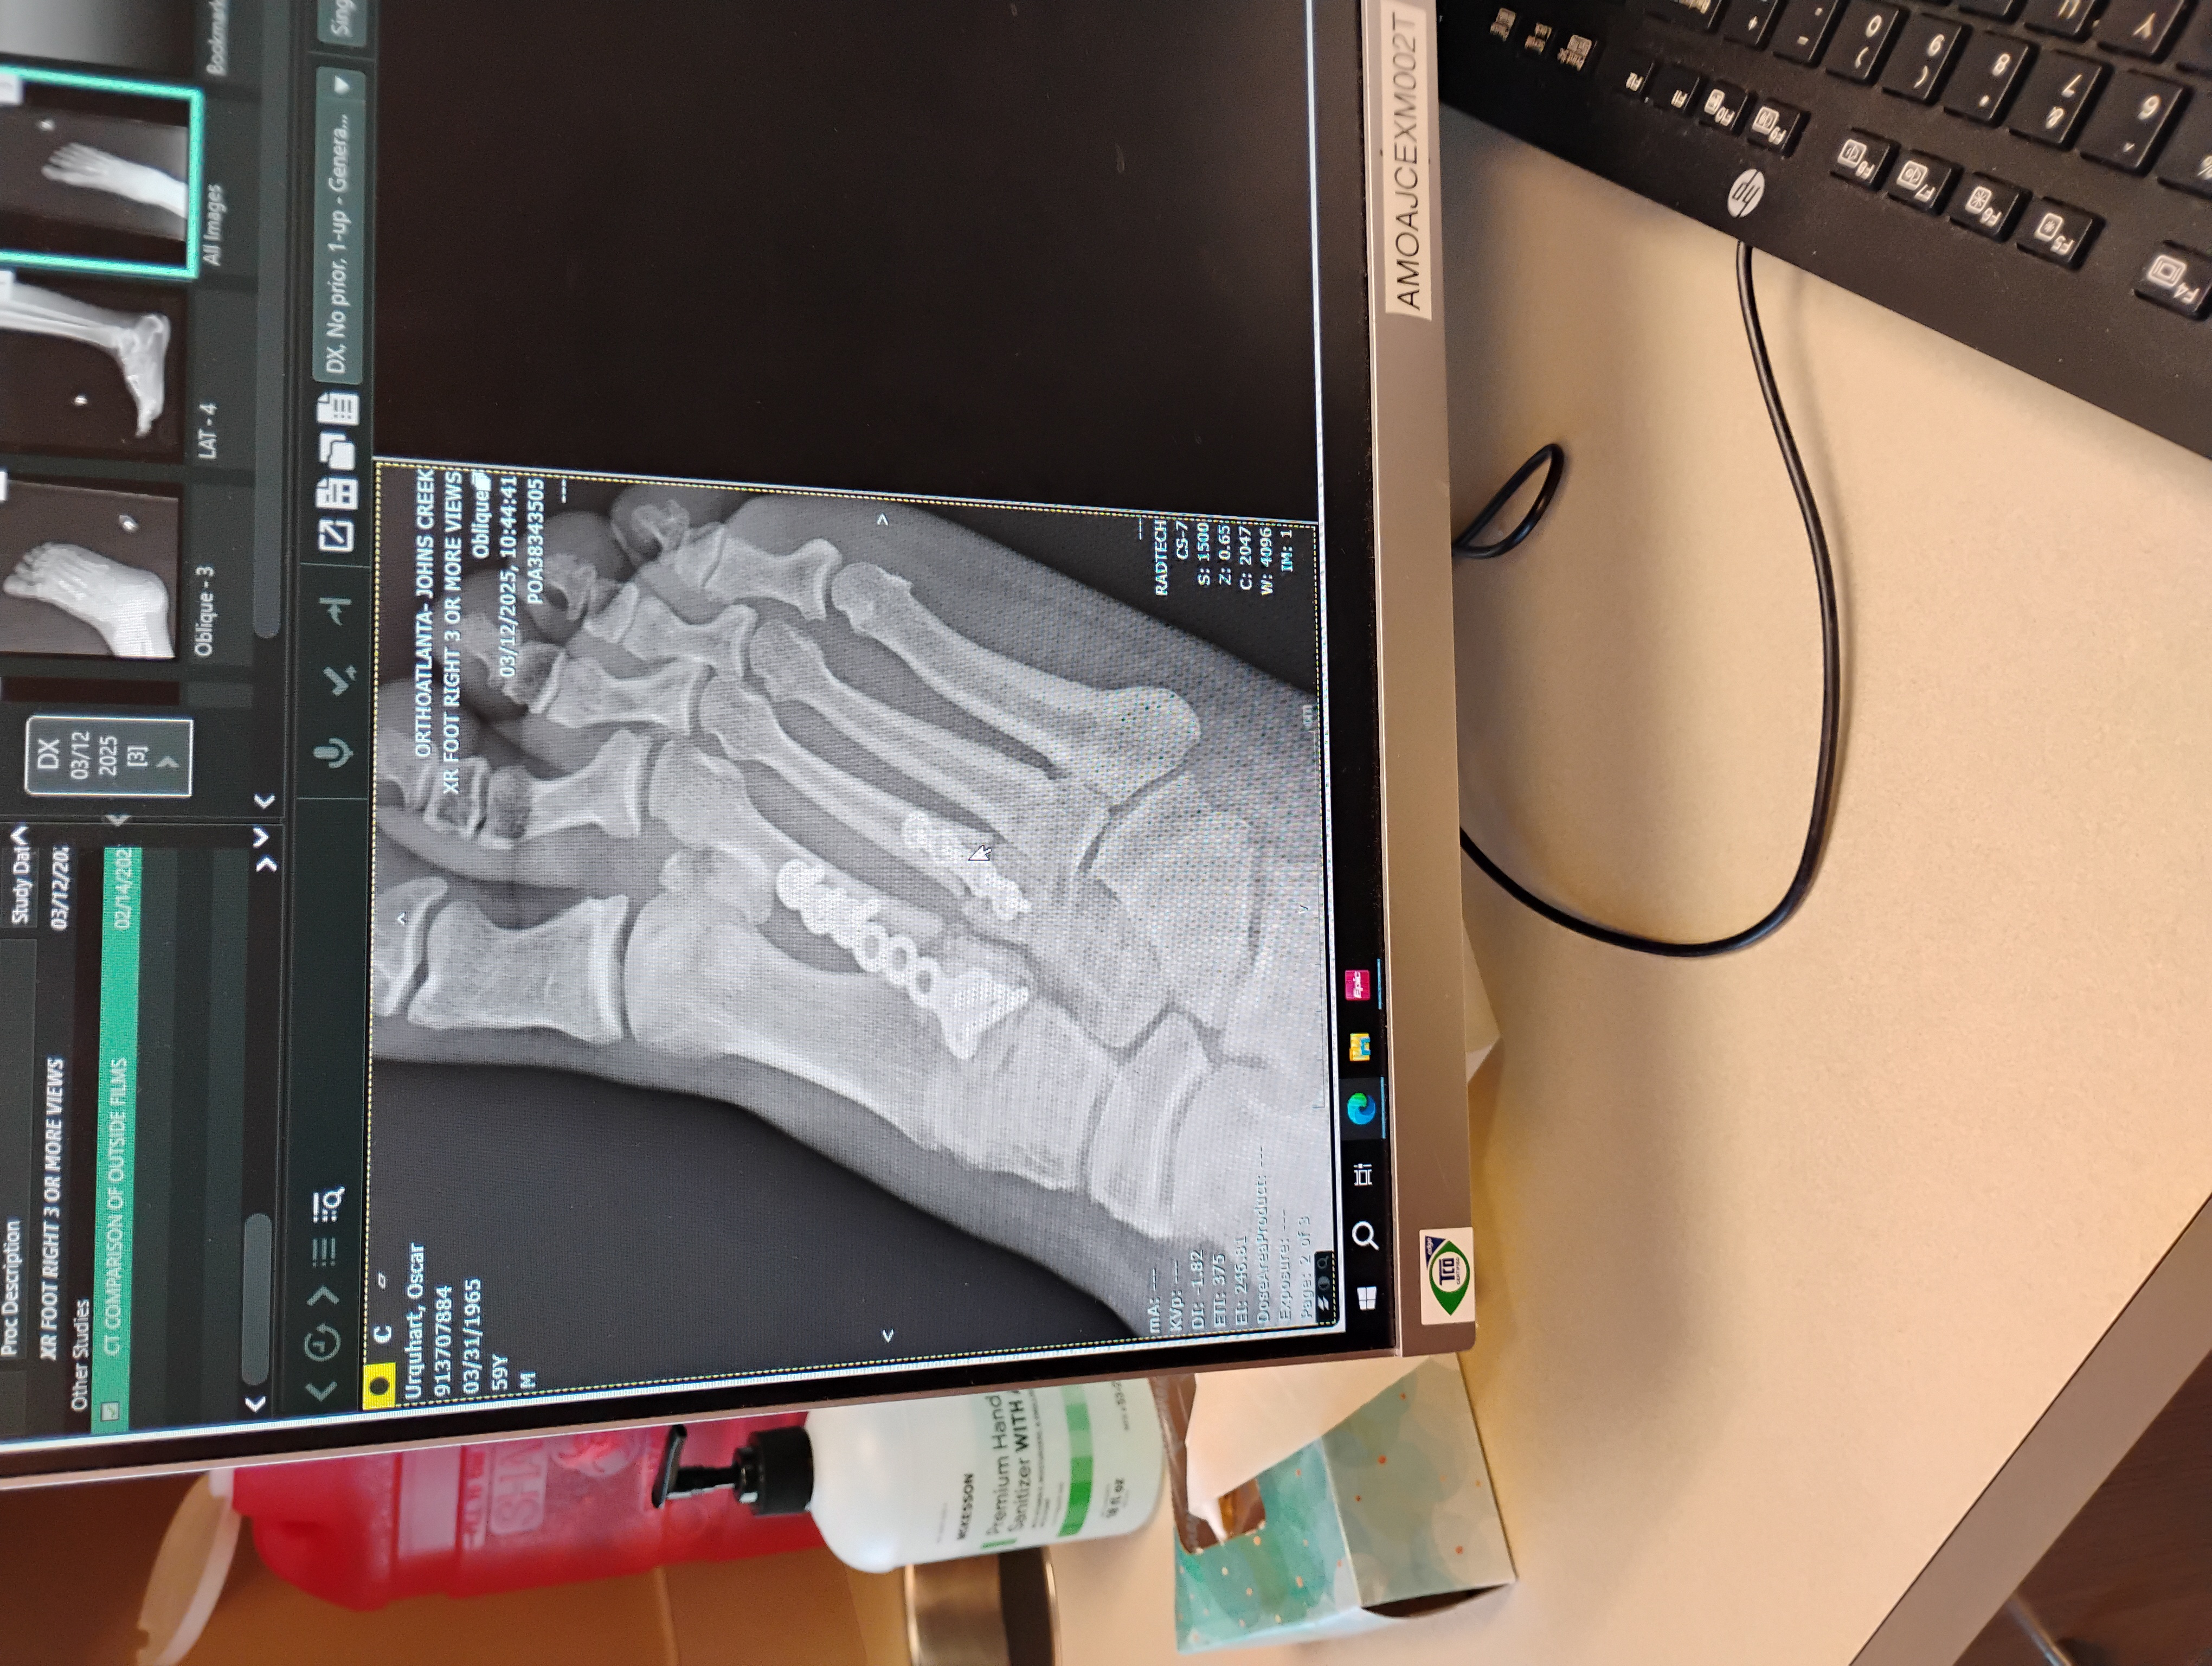

On January 29th my husband Oscar Keith Urquhart had a scissor lift rolled on to the top of his foot and stopped and it broke 3 bones in his foot which he had surgery for on February 27th at this time we do not know when he will be able to return to work